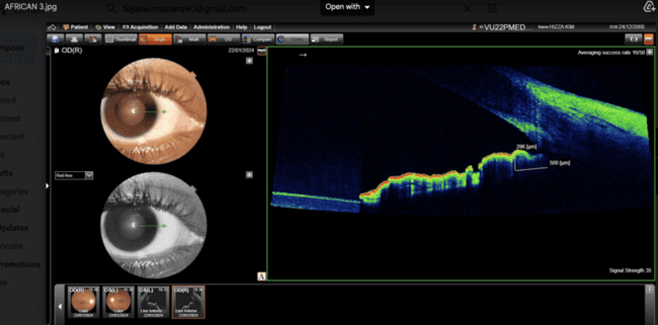

Volunteers Asians and Africans students selected from paramedical courses Gitam University, Visakhapatnam campus. In this analytical comparative  study, 400 eyes (100 Asians and 100 Africans), between the age of 18 to 35 years are selected for this study. Out  of 100 subjects  50 are males and 50 are females from Asian ethnicity and African ethnicity respectively. A comprehensive ophthalmic examination is carried out, includes Best Corrected visual acuity (BCVA) obtained after refractive correction, Anterior segment is evaluated by Slit lamp biomicroscopic examination, Fundus examination is carried out by + 78Ds lens,  Intra Ocular Pressure (IOP) recorded with Applanation tonometer. The cases with defective vision, IOP more than 21 mm of Hg, those who underwent LASIK, other Anterior segment diseases are excluded from this study. This study is conducted in the Department of Ophthalmology with the approval of Ethics committee of  Gitam Institute of Medical Sciences and Research, Visakhapatnam. All the cases are subjected to measurement of root of iris by the Optical coherent tomograph Topcon 3D OCT-1 Maestro 2 in static mode, 500 microns from the root of the iris. Nasal aspects of the root of the iris thickness of the Africans (Fig 1) and Asians are measured (Fig 2).

Fig 1: Iris thickness of African at T500 with 296 microns